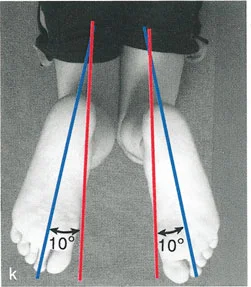

- فحص الدوران المحوري للأطراف (على سبيل المثال، محور الفخذ-القدم لدوران الساق).

الشكل 12-29أ، ب: الاختلافات في القياسات الإسقاطية الناتجة عن منظورين مرجعيين مختلفين (المتطابقات المنظرية). في المنظر الأمامي الخلفي بالنسبة للقطعة المرجعية الأمامية للركبة، تبدو الساق بـ 4.75 درجة من التقوس للداخل. أما بالنسبة للقطعة المرجعية الأمامية للقدم، فتبدو بـ 5.5 درجة من التقوس للخارج. تختلف قياسات الدوران أيضًا بناءً على منظور المراقب.